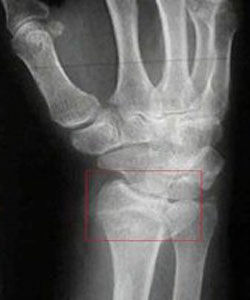

X線攝影:橈骨在距關節面3.0厘米左右處橫斷。正位片上骨折遠段向橈側移位,可與骨折近段有嵌插,下尺橈關節距離增大(分離)。橈骨下端關節面向尺側傾斜度減少,正常為20°~25°,骨折後可減小到5°~15°甚至消失;側位片上,橈骨遠端向背側移位,關節面掌側傾斜角度減少或消失,正常為10°~15°。

在老年人,骨折遠段可呈粉碎性骨折。